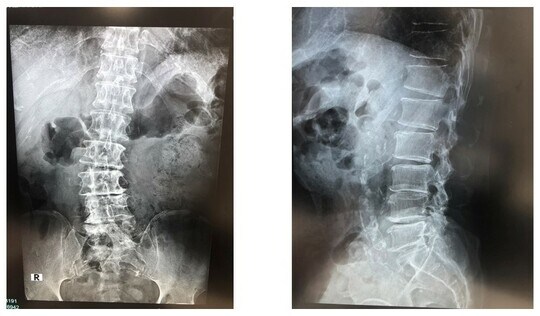

当院での初診当時は、痛みやしびれのため、右足を地面につけることもできない状態でした。安静にしていても、寝るときも痛みが生じ、100m先のコンビニにも歩いていくことができません。当院でレントゲンとCT検査を行い、前医から引き継いだMRI検査の画像を見たところ、はっきりと椎間板が傷んでいる様子がわかりました。

さらにTさんの場合、先述の椎間板ヘルニアと脊柱管狭窄症に加えて「変性側弯症(へんせいそくわんしょう)」も併発していました。

変性側弯症とは、脊椎が左右に曲がっている状態のこと。椎間板ヘルニアにこれらが合わさっているケースは決して珍しくなく、Tさんの場合もレントゲンなど画像検査の結果から、合併していることは明らかでした。